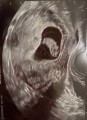

2024年07月23日 14:20

行ってきました! 産婦人科!! 今の大きさは‥19.2ミリ! 週数的には8週と6日らしい! もうすぐ、9週です! 3週間後に初めての検診が始まりますが‥ もう、心配しかない‥ 1回目、2回目とそ... 続きを読む

2024年07月19日 09:26

朝からめまいが酷く‥ 今、ゴロンしてます!! 血圧が下がり過ぎて‥ 起き上がれなかった‥ 今は画像を添付しときます(笑) ゴロンしてたらまだマシなので!ポイント稼いどこう! 今日はお仕事お休みし... 続きを読む

2024年07月16日 23:12

家です! 旦那とするのは家で十分やし! すぐ、お風呂入れて寝れるし

お金かからないので(笑) 今日は産婦人科いってきました! 心拍は確認できたので一安心! しかし‥ ある数値が低い為、流産の可... 続きを読む